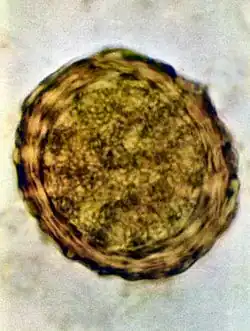

Fertile egg as can be seen in a microscope

Ascaris lumbricoides is characterized by its great size. Males are 2–4 mm (0.08–0.2 in) in diameter and 15–31 cm (5.9–12 in) long. The male's posterior end is curved ventrally and has a bluntly pointed tail. Females are 3–6 mm (0.1–0.2 in) wide and 20–49 cm (7.9–19 in) long. The vulva is located in the anterior end and accounts for about one-third of its body length. Uteri may contain up to 27 million eggs at a time, with 200,000 being laid per day. Fertilized eggs are oval to round in shape and are 45–75 μm (0.0018–0.0030 in) long and 35–50 μm (0.0014–0.0020 in) wide with a thick outer shell. Unfertilized eggs measure 88–94 μm (0.0035–0.0037 in) long and 44 μm (0.0017 in) wide.[9]